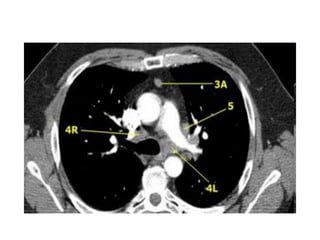

1. Khôùp öùc-ñoøn

2. Tónh maïch thaân caùnh tay ñaàu (T)

3. Cung ñoäng maïch chuû

4. Cöûa soå pheá chuû

5. Ñoäng maïch phoåi (T)

6. Thaân vaø ñoäng maïch phoåi (P)

7. Nhó (T)

8. Caùc buoàng tim

9. Khoang sau chaân hoaønh

CAÙC MAËT CAÉT CÔ BAÛN TRUNG THAÁT

Coù haïch nhoû tröôùc maïch maùu -3A

3. HAÏCH TRÖÔÙC MAÏCH MAÙU VAØ TRÖÔÙC SOÁNG

Khoâng naèm caïnh khí quaûn- naèm tröôùc maïch maùu (3A) hay sau thöïc quaûn tröôùc coät soáng (3P)

Haïch tröôùc maïch maùu -3A.

Haïch caïnh khí quaûn döôùi -4R.

4. HAÏCH CAÏNH KHÍ QUAÛN DÖÔÙI